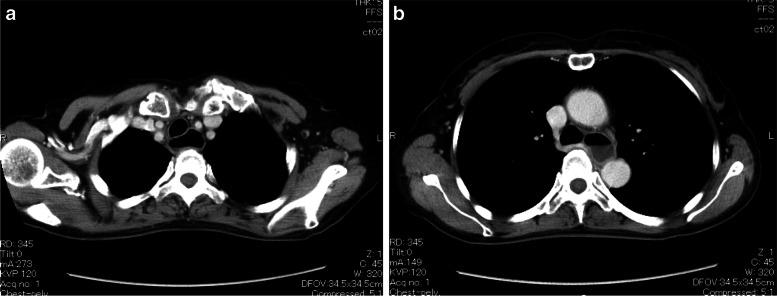

A 58-year-old woman was scheduled for orthopedic surgery under general anesthesia. She vomited a large amount of watery contents during anesthesia induction, and planned surgery was postponed. After recovery from anesthesia, she informed us that she usually had to drink a large amount of water to get food into her stomach and purged watery vomit every night before sleep. However, she attributed it to her constitutional problem, not to a specific disease. She was subsequently diagnosed with esophageal achalasia and underwent Heller myotomy with Dor fundoplication before her re-scheduled orthopedic surgery.

一名58岁女性计划在全身麻醉下进行骨科手术。她在麻醉诱导期间呕吐出大量水样内容物,计划中的手术被推迟。麻醉苏醒后,她告知我们她通常需要喝大量的水才能将食物送入胃中,并且每晚睡前都会吐出水样呕吐物。然而,她将此归因于自身的体质问题,而非特定疾病。随后她被诊断为食管贲门失弛缓症,并在重新安排的骨科手术前接受了贲门肌切开术加Dor胃底折叠术。